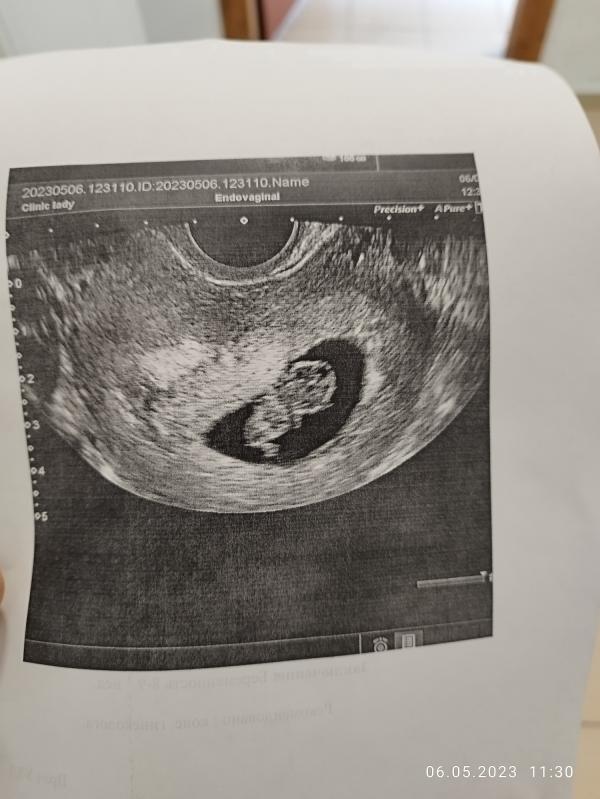

Узи 8 недель и 5 дней: развитие плода, сердцебиение и постановка на учет в ЖК. Делимся опытом!

Первое фото пузожителя 🙂 по узи 8нед 5 дней, по месячным 9нед.1день, думала разница будет больше,так как по дате зачатия совсем 7нед. 6дней. Вообщем растём, сердечко бьётся, на учёт в женской уже встала.